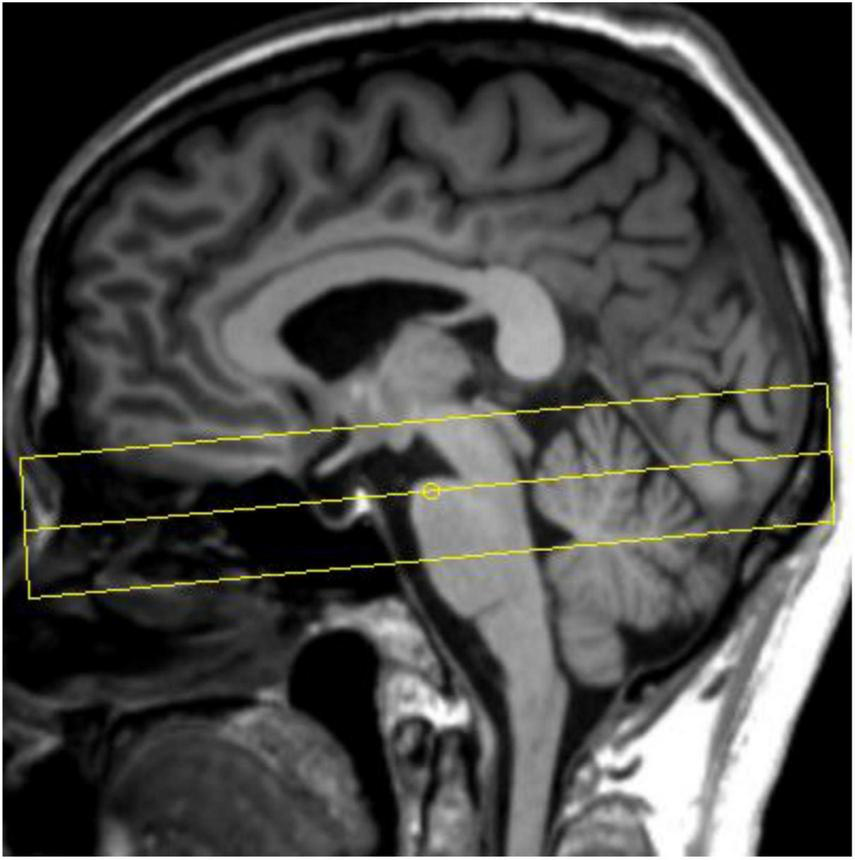

All participants underwent cranial MRI scans on a 3T MR scanner (Prisma, Siemens Healthcare, Erlangen, Germany) with a 64-channel phased array head coil. Routine sequence scans were first performed, including T1WI, T2WI, and diffusion weighted imaging (DWI), to exclude participants with structural abnormalities of the brain. Sagittal 3D-T1WI volumetric data were subsequently acquired using T1-weighted three-dimensional magnetization-prepared rapid acquisition gradient-echo sequence (3D MP-RAGE). The schematic diagram of NM-MRI scan is shown in Figure 2. NM-MRI imaging scan is performed: TR = 262.0 ms, TE = 3.01 ms, flip angle = 40°, 8 signal averages, FOV = 200 mm× 200 mm, voxel size = 0.6 mm× 0.6 mm× 3.0 mm, 10 slices, acquisition time 11 min 11 s.

FIGURE 2

Schematic diagram of neuromelanin-sensitive magnetic resonance imaging (NM-MRI) scan.